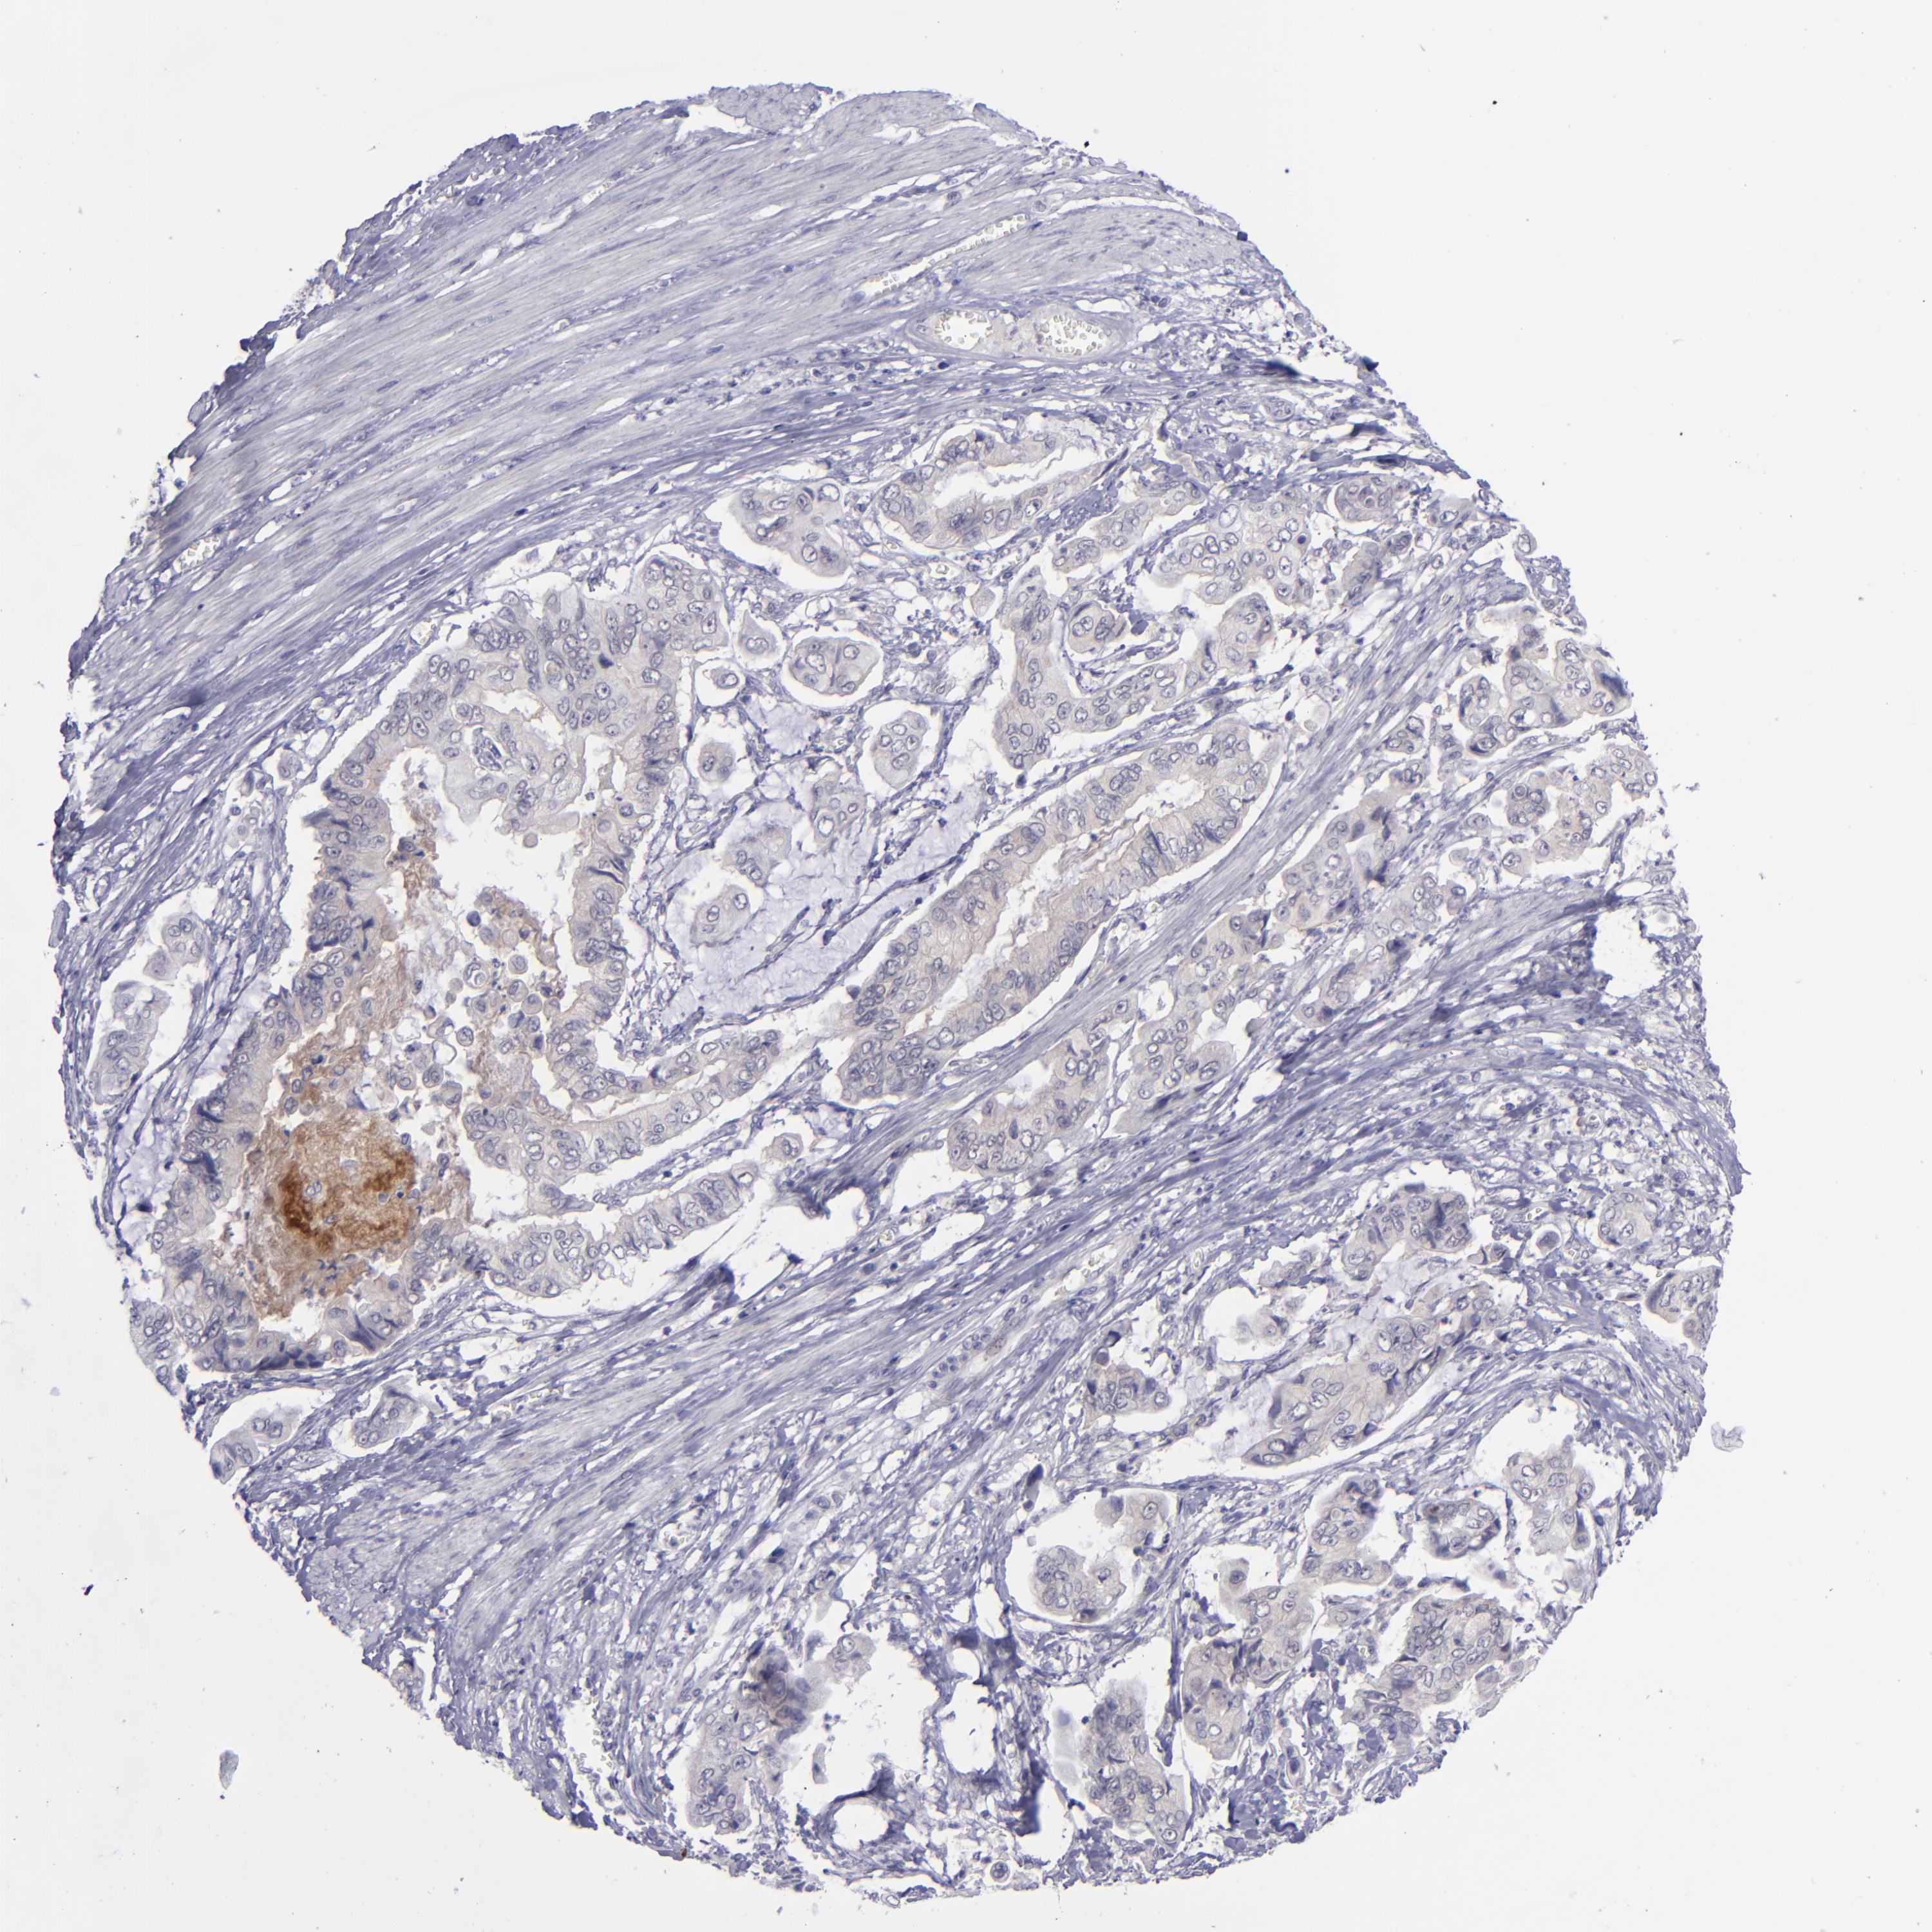

STOMACH CANCER - Protein expressioni

A mouse-over function shows sample information and annotation data. Click on an image to view it in a full screen mode. Samples can be filtered based on level of antibody staining by selecting one or several of the following categories: high, medium, low and not detected. The assay and annotation is described here.

Antibody stainingi

Antibody staining in the annotated cell types in the current human tissue is reported as not detected, low, medium, or high, based on conventional immunohistochemistry profiling in selected tissues. This score is based on the combination of the staining intensity and fraction of stained cells.

Each image is clickable and will lead to virtual microscopy that enables deeper exploration of all samples and also displays staining intensity scores, fraction scores and subcellular localization as well as patient and tissue information for each sample.

Antibody CAB002220

Adenocarcinoma, NOS